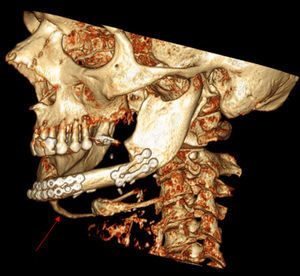

Se realizó una gammagrafía ósea que demostró una captación localizada de tecnecio en el maxilar inferior. Se realizó posteriormente una tomografía computarizada del cuello, la proyección axial maximum intensity projection (MIP) (fig. 1) y las imágenes en reconstrucción 3D (fig. 2) muestran una calcificación lineal anormal que se extiende desde el borde inferior de la mandíbula hacia el hioides, siguiendo el vientre anterior del músculo digástrico.